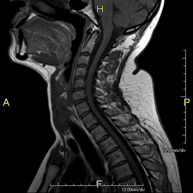

- Cervical spine MRI

This non-invasive diagnostic procedure uses an electromagnetic field and radio waves (from a transmitter and receiver) to acquire high-definition anatomical images of the cervical spine. It is a radiation-free procedure. Indicated for: trauma, spinal degeneration, hernias.

- Cervical + thoracic spine MRI

This non-invasive diagnostic procedure uses an electromagnetic field and radio waves (from a transmitter and receiver) to acquire high-definition anatomical images of the cervical and thoracic spine. It is a radiation-free procedure. Indicated for: trauma, spinal degeneration, hernias.